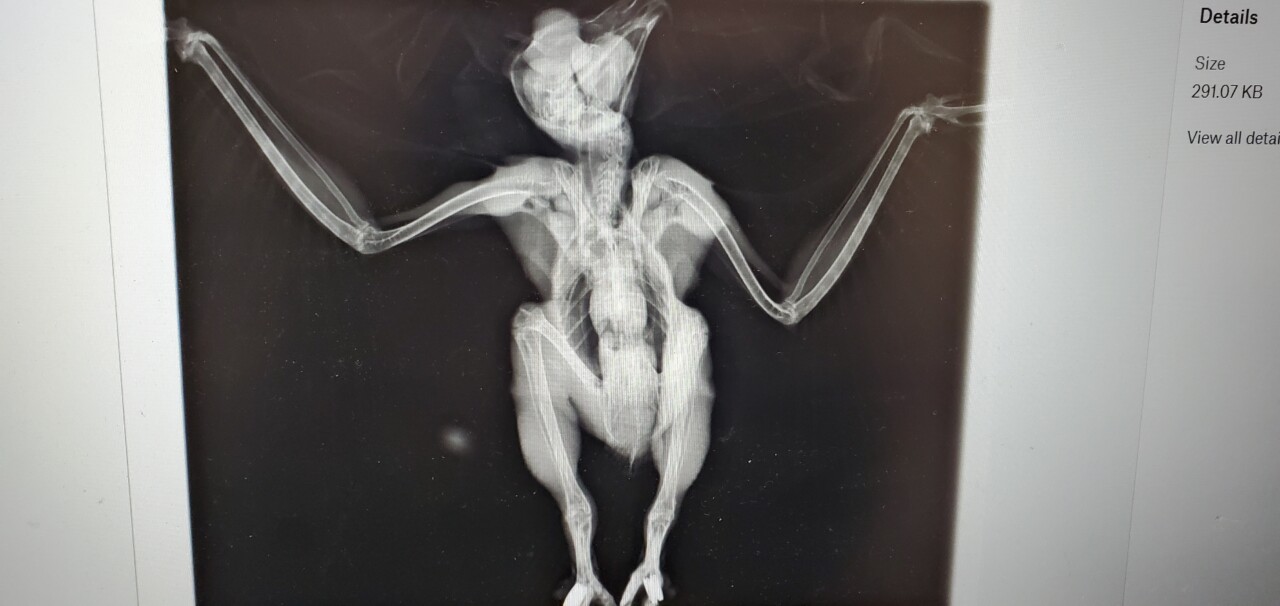

As a part of their diagnostic evaluation, the rehabilitation staff at VINS took some x-rays of Oberon that we thought we’d share with you — it isn’t every day you get to see the skeleton and musculature of an owl! This might help you visualize just how much of Oberon’s appearance is filled out with his insulating feathers